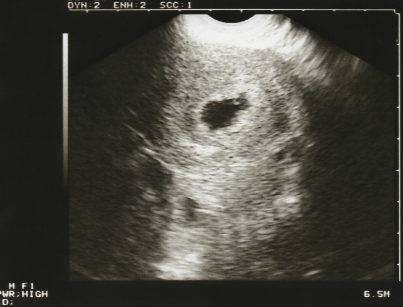

태낭이 보인다.

자궁 안에 아기를 감싸고 있는 주머니인 태아의 모습을 볼 수 있다. (임신 5주경)